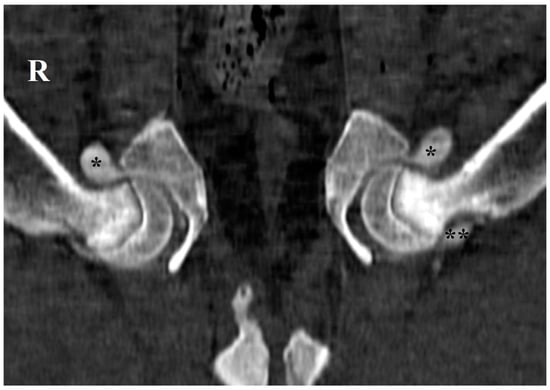

2.2. Radiographic Hip Stress View and Hip Laxity Measurement

3. Results